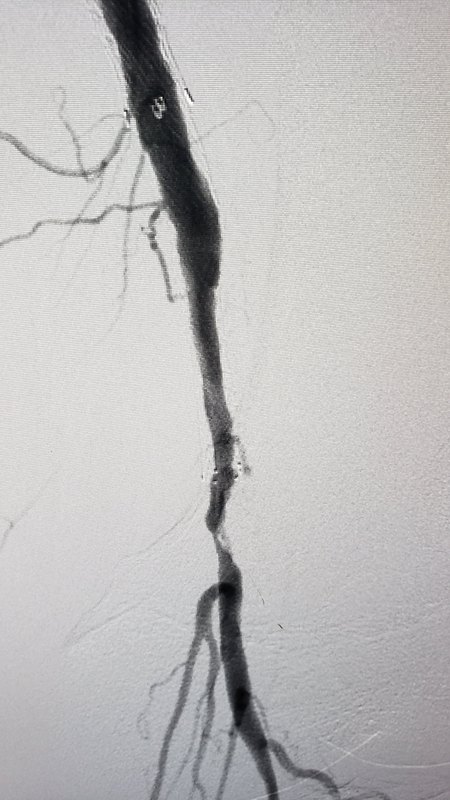

十年反復(fù)治療的老姚,病情持續(xù)加重,今天終于再下決心,進(jìn)行了第九次介入治療,因為疤痕,穿刺是極大考驗,手術(shù)技巧是成功的關(guān)鍵,成功打通閉塞段腘動脈和脛腓干,效果良好!